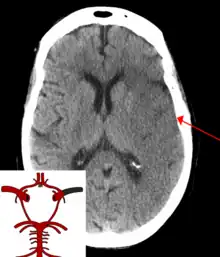

| CT scan of the brain showing a prior right-sided ischemic stroke from blockage of an artery. Changes on a CT may not be visible early on.[1] | |

The main risk factor for stroke is high blood pressure.[6] Other risk factors include tobacco smoking, obesity, high blood cholesterol, diabetes mellitus, a previous TIA, end-stage kidney disease, and atrial fibrillation.[2][6][7] An ischemic stroke is typically caused by blockage of a blood vessel, though there are also less common causes.[12][13][14] A hemorrhagic stroke is caused by either bleeding directly into the brain or into the space between the brain's membranes.[12][15] Bleeding may occur due to a ruptured brain aneurysm.[12] Diagnosis is typically based on a physical exam and supported by medical imaging such as a CT scan or MRI scan.[8] A CT scan can rule out bleeding, but may not necessarily rule out ischemia, which early on typically does not show up on a CT scan.[9] Other tests such as an electrocardiogram (ECG) and blood tests are done to determine risk factors and rule out other possible causes.[8] Low blood sugar may cause similar symptoms.[8]

For diagnosing ischemic (blockage) stroke in the emergency setting:[64]

- CT scans (without contrast enhancements)

- sensitivity= 16% (less than 10% within first 3 hours of symptom onset)

- specificity= 96%

CT scans may not detect an ischemic stroke, especially if it is small, of recent onset, or in the brainstem or cerebellum areas. A CT scan is more to rule out certain stroke mimics and detect bleeding.[9]